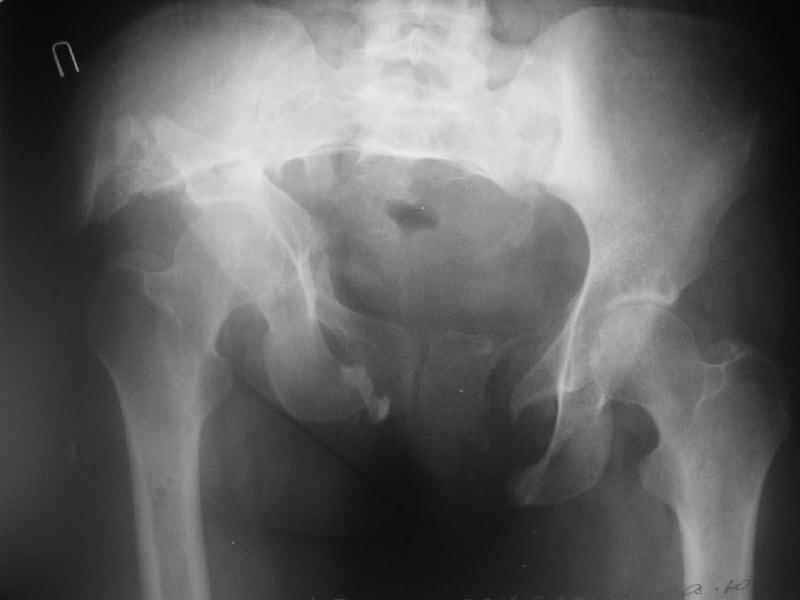

Some additional data. Her main complaints are:

-pain in the left SI joint, the right is painless;

-limb shortening (walks with shoe raise, no walking aid)

-scoliosis and extra-lordosis

-low back pain

-unable to stand more than 20-30 minutes

-unable to sleep without inflatable rubber pad under the sacrum and bolsters under knees.

-unable to sit comfortably

Majeed score is 41.

X-rays and more CT - see attached.